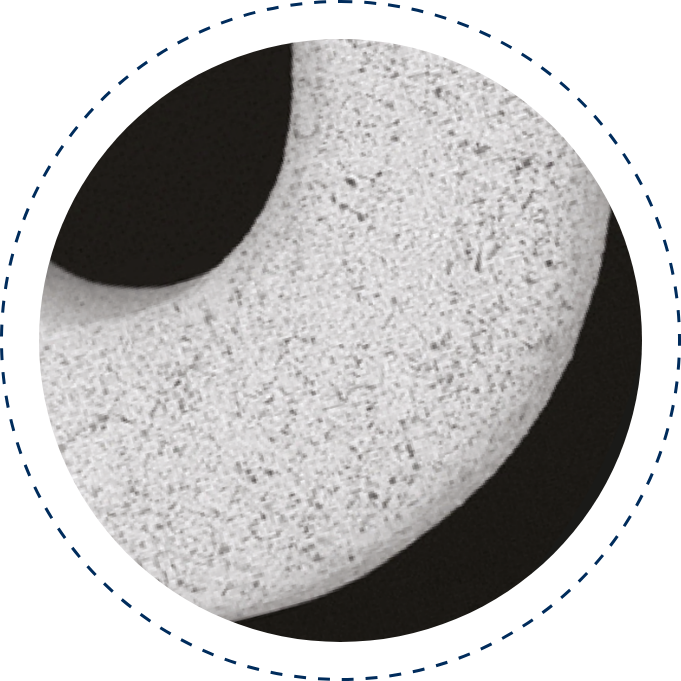

Microporous Surface (PEARL)

The PEARL surface, combined with a biodegradable polymer, enhances endothelialization, reduces restenosis and thrombosis, and ensures controlled drug release, delivering optimal performance as a safe and effective DES technology.